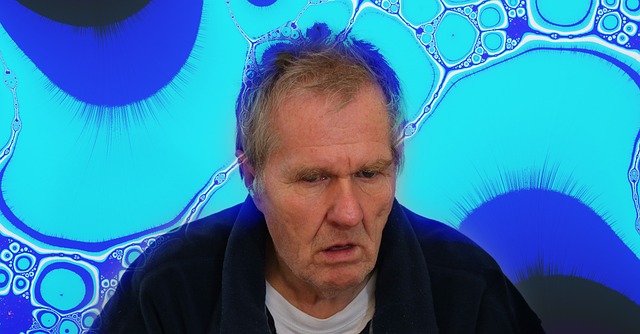

Pacient cu boala Alzheimer